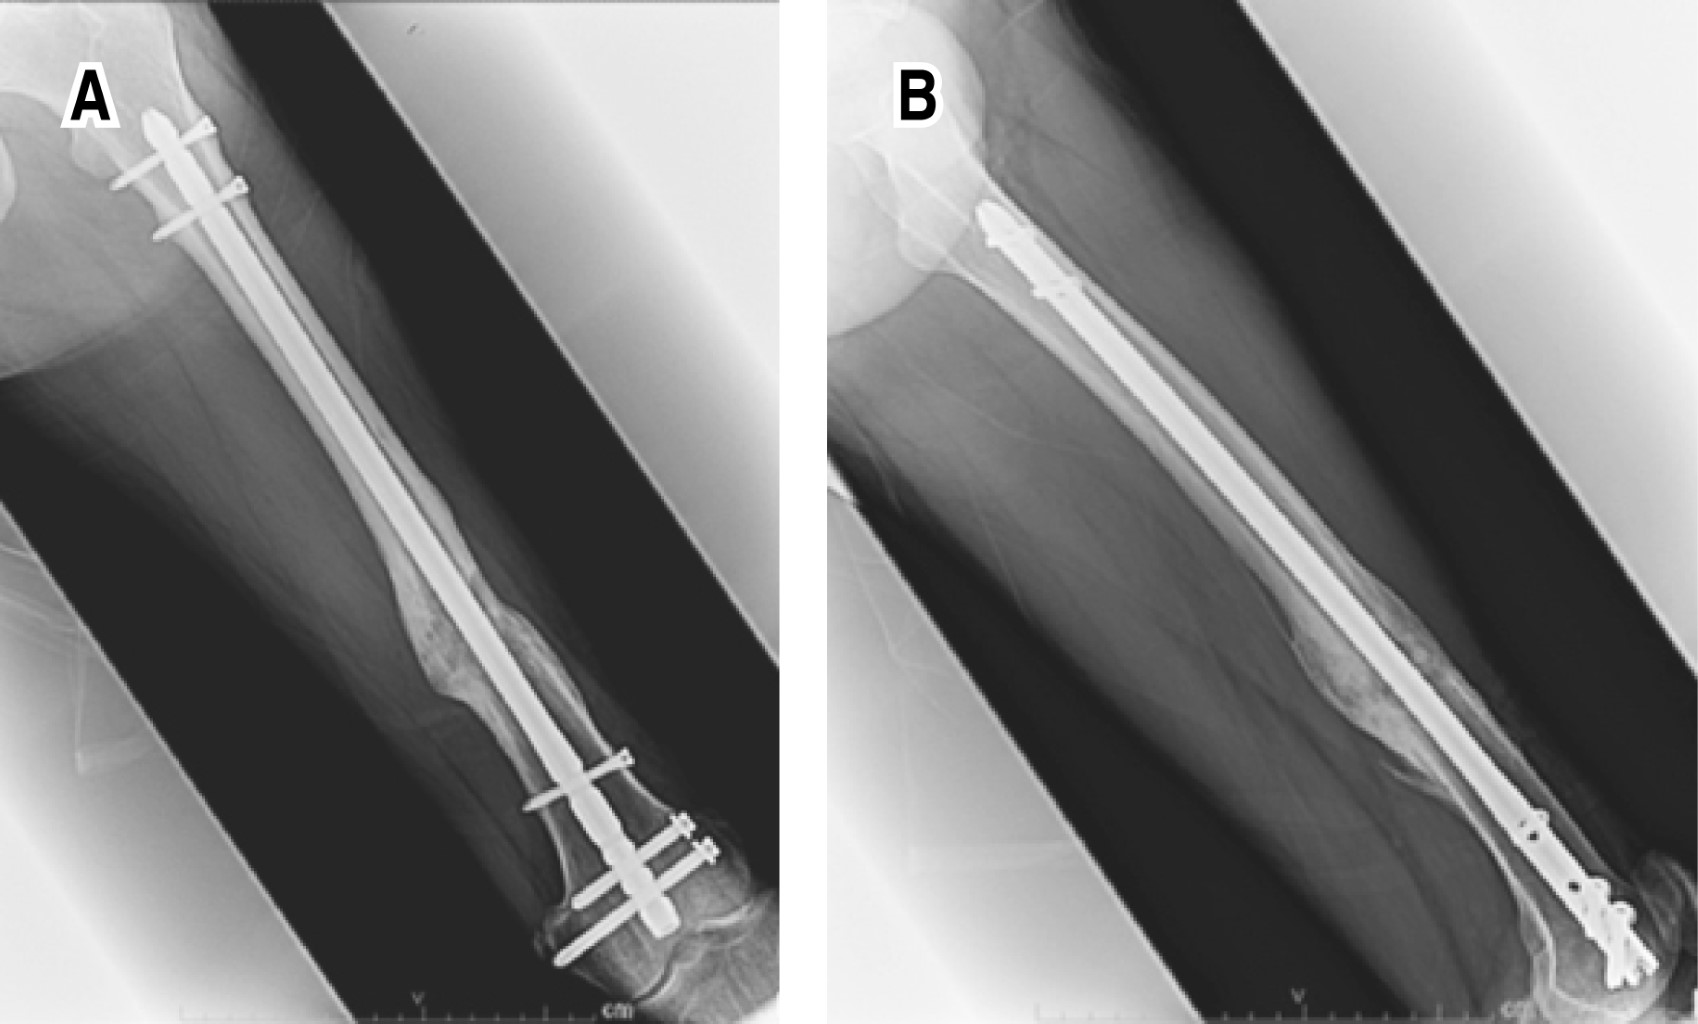

Con el seguimiento del paciente a los uno, dos, tres, seis, ocho, 10, 12 y 24 meses obtuvimos una evolución clínica y radiográfica favorable. Así, pudimos apreciar formación de puentes óseos sobre la cortical medial en la radiografía a los tres meses, por lo que se indicó apoyo parcial progresivo de la extremidad con muletas hasta llegar al apoyo total, lo que mejoró la formación del callo óseo en el control radiográfico a los seis meses (Figura 3), y posteriormente se observó regeneración ósea total a los 24 meses (Figura 4). En la actualidad, el paciente presenta marcha sin alteraciones y rangos de movilidad en rodilla y cadera completos.

Bajo el mismo seguimiento a ambos pacientes, observamos una evolución clínica y radiográfica favorable, y a los dos meses se encuentra en la radiografía formación de puentes óseos sobre la cortical medial, por lo que se indica apoyo total de la extremidad. Se continúa con evolución satisfactoria, presenta regeneración ósea total en su control radiográfico a los seis meses. Al día de hoy el paciente presenta marcha sin alteraciones, rangos de movilidad en rodilla y cadera completos, y está incorporado en su totalidad a sus actividades laborales y cotidianas (Figura 6).

Figura 3

Figura 6